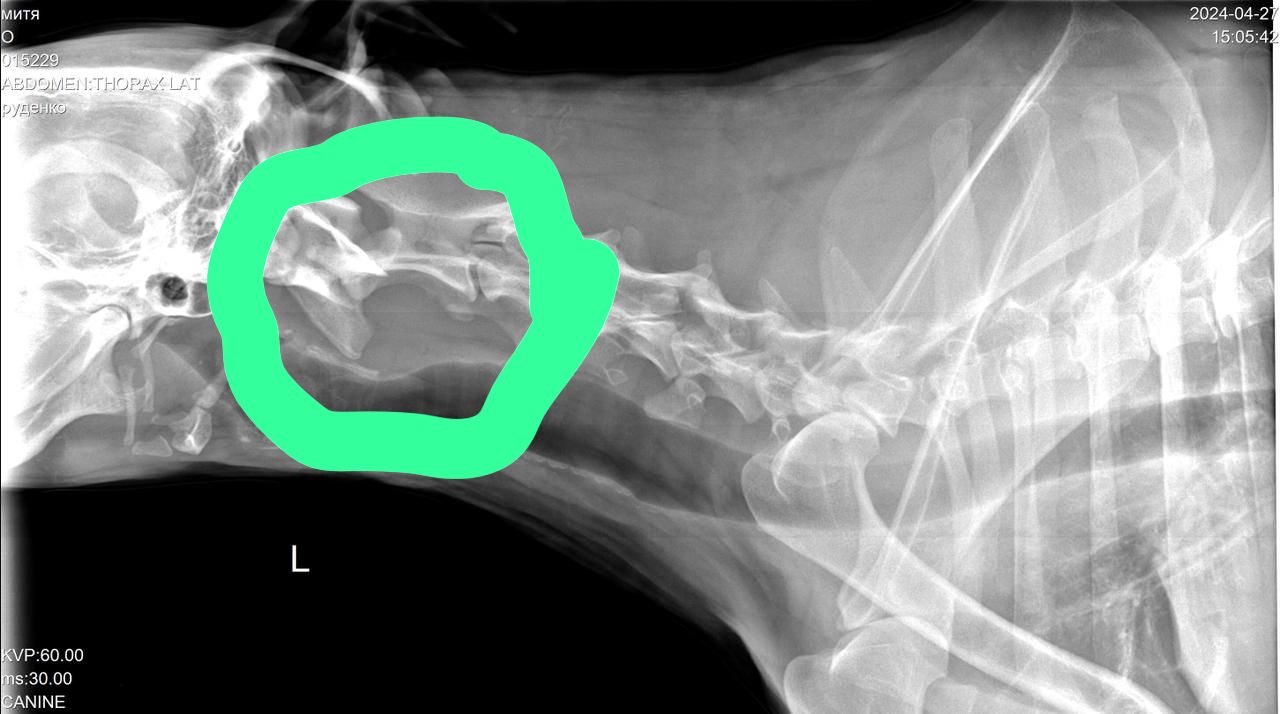

Сегодня Катюша возила Митю на рентген.

Вложения